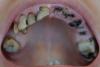

_Marina_ Опубликовано 3 августа, 2013 Поделиться Опубликовано 3 августа, 2013 Здравствуйте.Проконсультируйте меня, пожалуйста. Подлежат ли все имеющиеся зубы удалению с последующим полным протезированием на имплантах или что-то можно полечить? Верхние 6, 7 слева и нижняя 5 справа выдвинулись из-за длительного отсутствия антагонистов. Верхняя 7 справа мигрировала вбок. Если эта инфо имеет значение для оценки перспектив сохранения зубов (ну вдруг , то справочно: многие родственники по линии одного из родителей полностью теряли зубы к 20-30 годам, мне 33 года. Причина: кариес дентина. Посещения стоматологов с выполнением предписаний видимым образом не приостанавливали процесс разрушения. Это уже потеряло оттенок трагичности, сколь незыблемо и как-то даже традиционно что ли сыпятся мои зубки Снимок прилагаю.Буду благодарна, если уделите внимание моему вопросу. Ссылка на комментарий

_Marina_ Опубликовано 4 августа, 2013 Автор Поделиться Опубликовано 4 августа, 2013 Фото прилагаю. На предыдущем панорамном снимке еще фигурируют удаленные в течение прошедшего месяца:Справа на в.ч. – 8Справа на н.ч – 6, 7 (случился первый в жизни флюс) Ссылка на комментарий

Bier Опубликовано 4 августа, 2013 Поделиться Опубликовано 4 августа, 2013 Пожалуй нужно вести речь о тотальном удалении и имплантации, часть зубов можно сохранять как временные опоры для временного протезирования. 1 Ссылка на комментарий